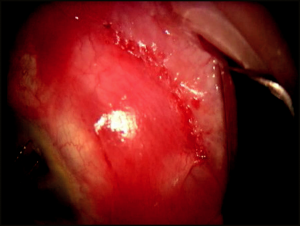

A peripheral iridectomy is performed to prevent obstruction/incarceration of the iris in the sclerectomy. The ideal iridectomy should be larger than the sclerectomy in all dimensions (wide at its base but short vertically to avoid iatrogenic polycoria and its associated monocular diplopia). With the scleral flap lifted, the iris is grasped 0.5 mm from the iris root and retracted through the sclerotomy. The scissors are opened enough to encompass the retracted iris, and then in one smooth cut, the iridectomy is made (Figure 4-7). The iris is reposited with a stream of balanced salt solution or by closing and gently massaging over the scleral flap. Upon completion of the iridectomy, the surgeon should have a view of the ciliary processes and occasionally the lens equator. If iris remnants or ciliary processes occlude the sclerectomy, these should be excised only with great caution because it is exceedingly easy to damage the lens or hyaloid face.